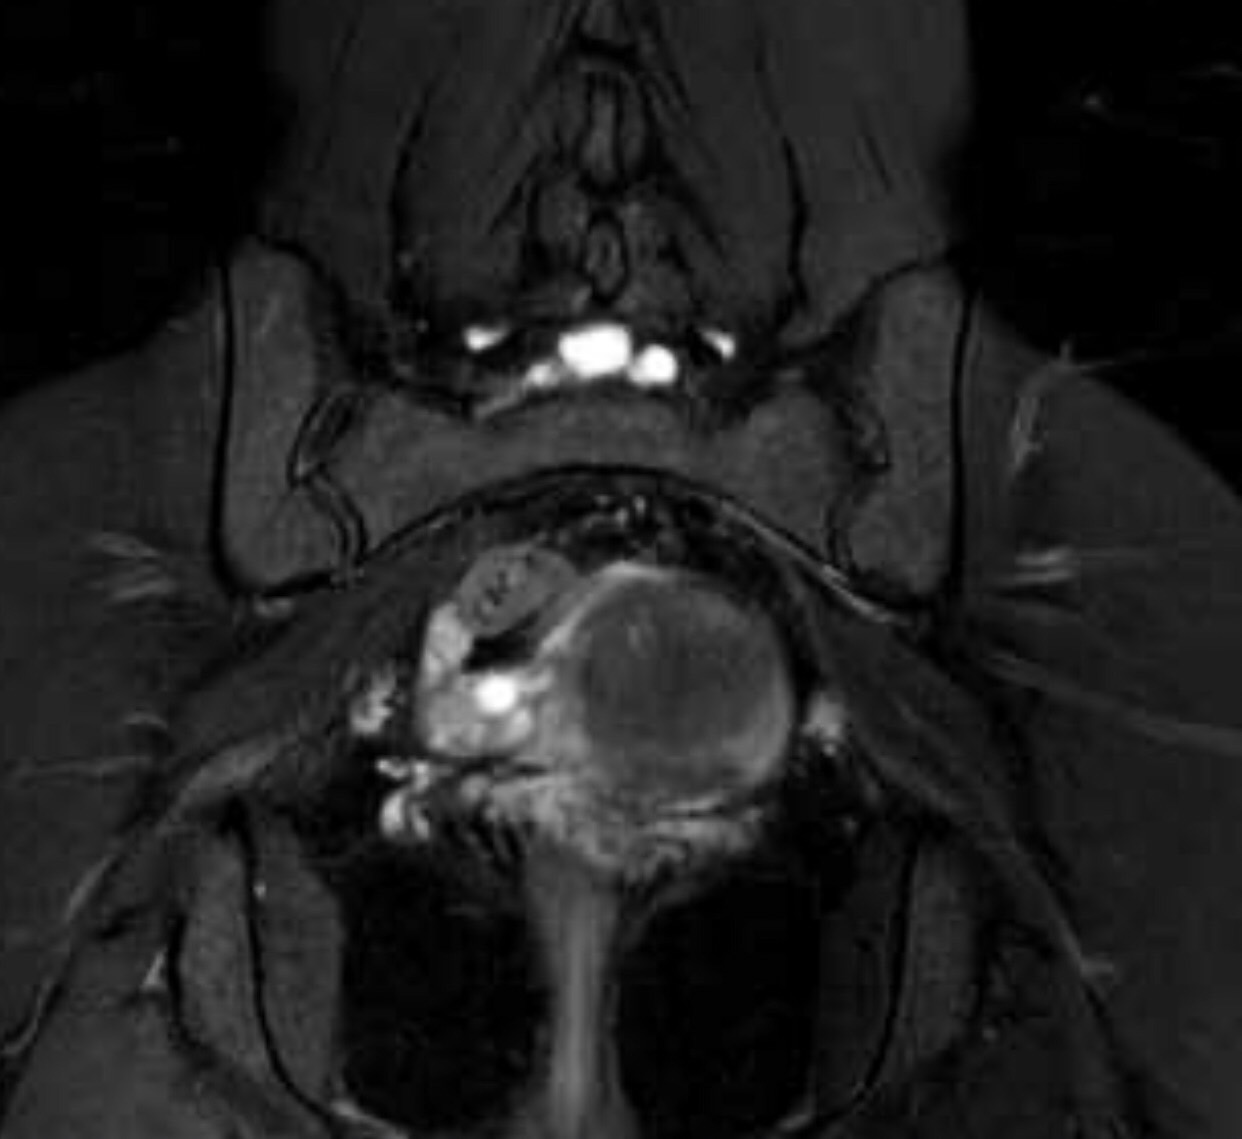

มีใครช่วยดูภาพ MRI Pelvis ของเราได้ไหมค่ะ

เรามีอาการทางประสาท ปวดแสบปวดร้อนที่กล้ามเนื้อขาอ่อน ชาขาลงเท้าเป็นบางครั้ง ส่วนมาจะเจ็บๆคันเหมือนโดนมดแดงไฟกัด บริเวณขาอ่อนด้านใน บางทีก๋กล้ามเนื้อสะโพกกับขาหนีบล็อกหกเกร็ง สะโพกรู้สึกหกเกร็งขาดความยืดหยุ่นเหมือนหนังยางที่ยึดแล้วมันปริแตกเป็นริ้ว เพราะหมดสภาพ บางทีก็แสบบริเวณกล้ามเนื้อเหนือหัวเข่า เรากำลังตามหาผู้ใจบุณช่วยวิเคราะห์ผล MRI ให้เราได้หลังไมค์มาเลนค่ะ เรายินดีส่งไฟล์ที่เป็น Full Version ให้ทางไลน์

จากรูปจุดขาวๆก้อนเล็กคืออะไรค่ะ